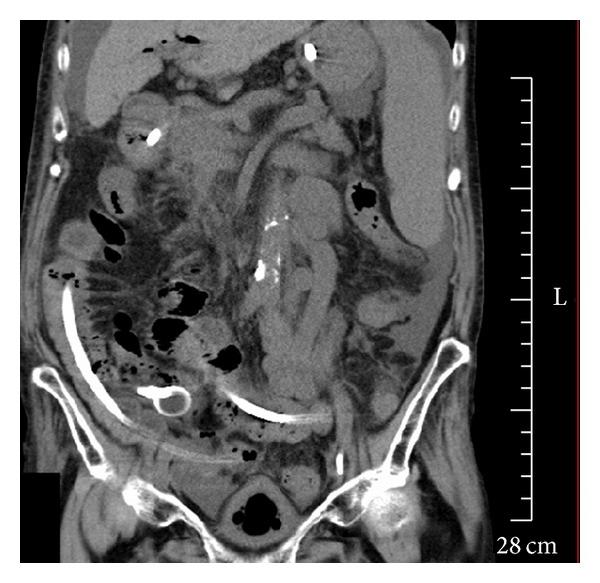

An 85-year-old woman was an outpatient treated at Tokyo Rosai Hospital for cirrhosis caused by hepatitis B. She had previously been diagnosed as having common bile duct stones, for which she underwent endoscopic retrograde cholangiopancreatography (ERCP). However, as stone removal was unsuccessful, a plastic stent was placed after endoscopic sphincterotomy. In October 2012, the stent was replaced endoscopically because she developed cholangitis due to stent occlusion. Seven days later, we performed ERCP to treat recurring cholangitis. During the procedure, the stone was successfully removed by a balloon catheter when cleaning the common bile duct. The next day, the patient developed abdominal pain, abdominal distension, and nausea and was diagnosed as having gallstone ileus based on abdominal computed tomography (CT) and abdominal ultrasonography findings of an incarcerated stone in the terminal ileum. Although colonoscopy was performed after inserting an ileus tube, no stone was visible. Subsequent CT imaging verified the disappearance of the incarcerated stone from the ileum, suggesting that the stone had been evacuated naturally via the transanal route. Although it is extremely rare for gallstone ileus to develop as a complication of ERCP, physicians should be aware of gallstone ileus and follow patients carefully, especially after removing huge stones.

一名85岁女性因乙型肝炎导致肝硬化,在东京Rosai医院接受门诊治疗。她此前被诊断患有胆总管结石,并接受了内镜逆行胰胆管造影术(ERCP)。然而,由于结石清除未成功,在内镜括约肌切开术后放置了塑料支架。2012年10月,因支架阻塞导致胆管炎,她接受了内镜下支架置换。七天后,我们进行ERCP治疗复发性胆管炎。在手术过程中,清理胆总管时通过球囊导管成功取出结石。第二天,患者出现腹痛、腹胀和恶心,根据腹部计算机断层扫描(CT)和腹部超声检查结果显示回肠末端有嵌顿结石,被诊断为胆石性肠梗阻。尽管在插入肠梗阻导管后进行了结肠镜检查,但未发现结石。随后的CT成像证实回肠中的嵌顿结石消失,表明结石已通过经肛门途径自然排出。尽管胆石性肠梗阻作为ERCP的并发症极为罕见,但医生应意识到胆石性肠梗阻并仔细观察患者,尤其是在取出巨大结石后。